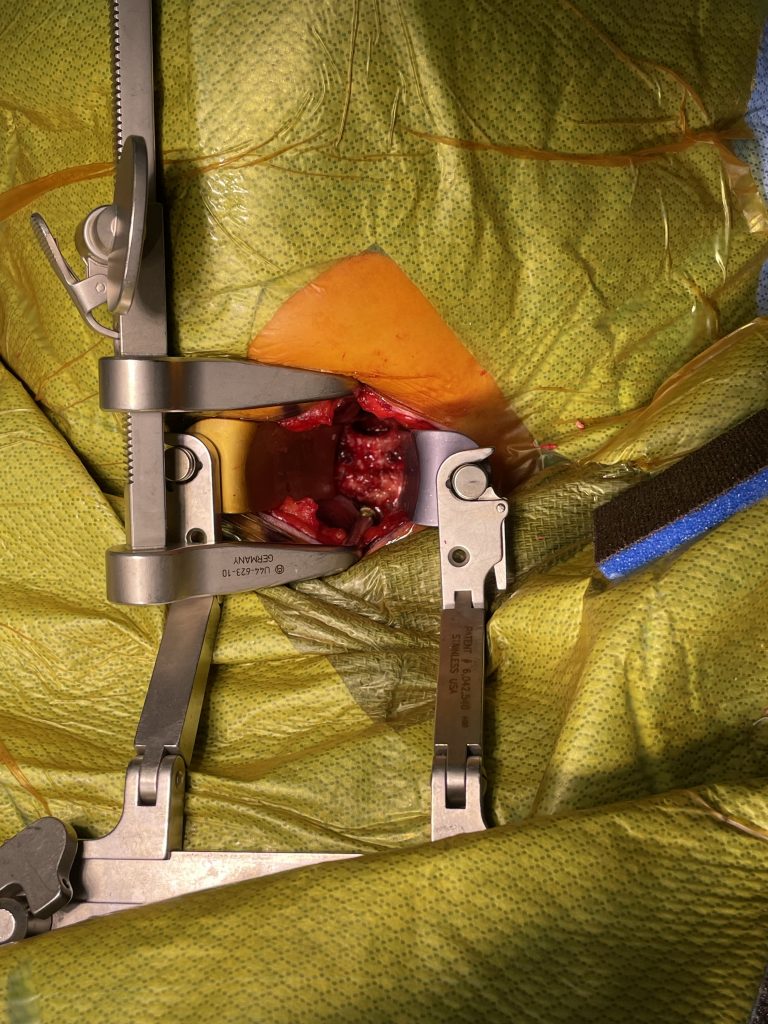

Here is the case of a 51 year-old female who had a ten year history of severe neck pain with severe right arm pain, numbness, and weakness. She weighed over 300 pounds. She had failed all means of conservative management including medicines, physical therapy, chiropractic care, and epidurals. MRI demonstrated a reverse of the normal curvature of the cervical spine with large disc osteophyte complexes compressing the spinal cord (Fig 1). The C4-5 disc osteophyte was larger causing severe anterior compression of the spinal cord, worse on the right side (Fig 2). This correlated with the patient’s clinical findings. Therefore surgery was recommended. Patient underwent an anterior cervical discectomy and fusion with a plate from C4-C6. We were able to get her into a good position. Although there was a very deep exposure through the fat layer, it was not too bad to expose the face of the spine (Fig 3). Because there is less muscle, tissue planes open up actually easier sometimes particularly in women because of a relative decrease in muscle mass. The same goes for exposure of the lumbar spine. The majority of “herniated discs” in the cervical spine are actually bony protrusions we call osteophytes. After you clear away all the other cartilage that is the soft part of the disc, the way to get rid of that C4-5 osteophyte which acts like a sheet of bone at the posterior aspect of the disc space, is to drill it down to a fine shell and remove it with a special tool. This tool is called a Kerrison and has a very thin footplate that allows a plane between the osteophyte and dura which is being compressed and bites away this bone. The patient had good relief of her symptoms postoperatively.

Fig 3: Intraoperative photo showing a deep exposure with deep retractors to access the anterior cervical spine